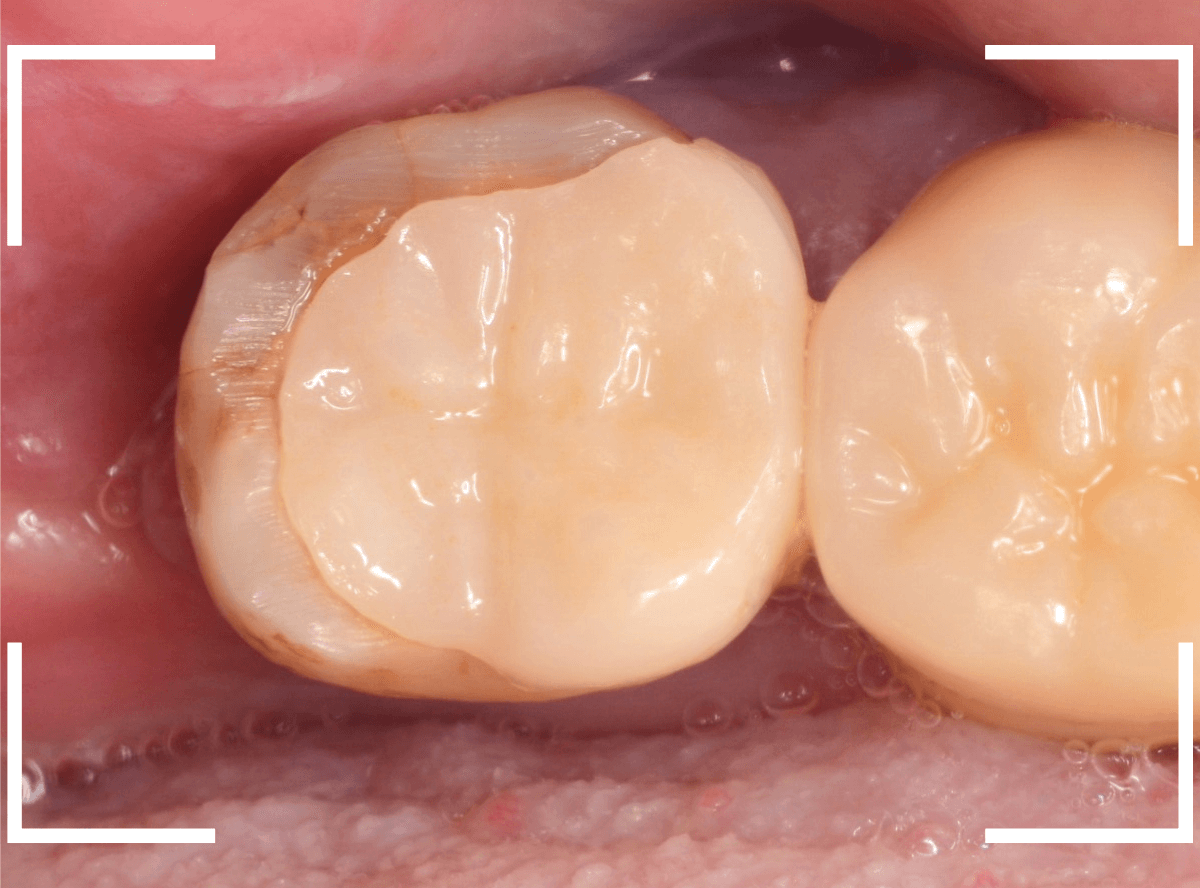

「奥歯で物を噛むと痛い」という患者さんのケースです。

検査をすると、上の一番奥の歯がグラグラです。

レントゲン写真で確認します。